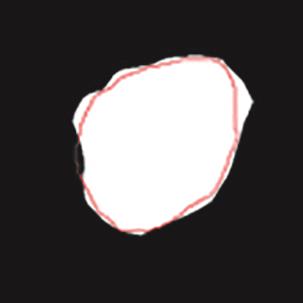

乳腺癌是全球女性最常见的恶性肿瘤之一,准确的病变分割对于乳腺癌的早期诊断与治疗具有重要意义。然而,由于病变形态的多样性以及超声成像机制的复杂性,现有基于深度学习的乳腺超声图像病变分割方法在分割准确性方面仍面临巨大挑战。为进一步提升乳腺超声图像中病变区域的分割精度,该文基于经典U-Net架构,提出了一种新型乳腺超声图像病变分割网络(CWSASKM-BBAM-Net)。首先,在网络中引入逐通道空间自适应选择核卷积模块(CWSASKM),根据不同通道的语义特征为每个空间位置自适应选择感受野大小,以增强多尺度信息的建模能力;然后,引入双向边界感知机制(BBAM),通过融合正向与反向注意力,对目标显著区域及其边界进行协同建模,同时逐步提升对非显著区域与病变区域的区分能力,以进一步强化边界信息的表达;最后,在3组公开乳腺超声图像数据集(BUSI、UDIAT和STU)上开展分割实验。结果表明:该方法在数据集BUSI上的杰卡德指数、精确率、召回率和Dice相似系数分别为71.97%、82.85%、81.40%和80.44%,较次优方法分别提升1.69、1.05、1.28和1.84个百分点;在数据集UDIAT上,这4项指标分别达到78.14%、88.31%、86.73%和86.10%,较次优方法分别提升了2.75、2.04、0.56和2.01个百分点;在外部数据集STU上,该方法也取得了优于其他方法的整体表现。实验结果表明,CWSASKM-BBAM-Net在乳腺超声图像分割任务中展现出更优的整体性能。